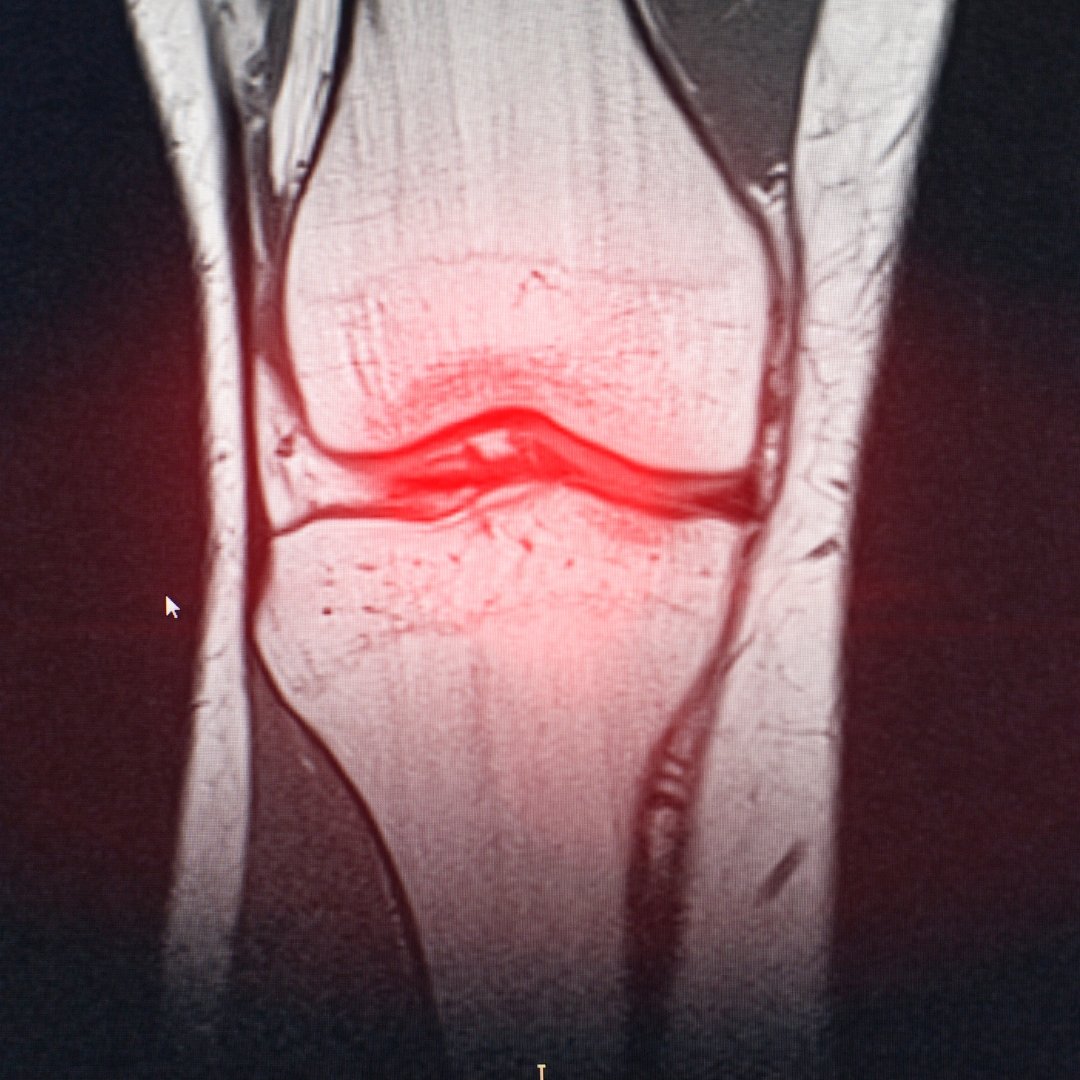

– МРТ для оцінки стану хряща